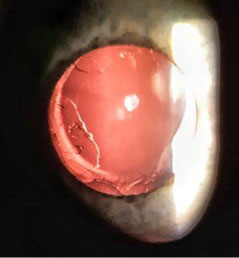

In both eyes: anterior chambers — deep, pupils were round, the IOLs were centered in the capsule bag, the posterior capsulorhexis were round. The right eye: the optical zone was transparent, the left eye: lens epithelial cells were in the optical zone on the posterior surface of the IOL (fig. 1, 2). The fundus of the eye was examined after the instillation of mydriatic. The optic nerve head is pale pink, with clear boundaries. Excavation of the optic nerve disc is widened, deep. According to OCT data the retinal nerve fiber layer (RNFL) and the ganglion cell complex were within normal limits, the macular region was normal.

Fig. 1. Patient's right eye, posterior capsulorhexis, rounded. The optical zone is transparent